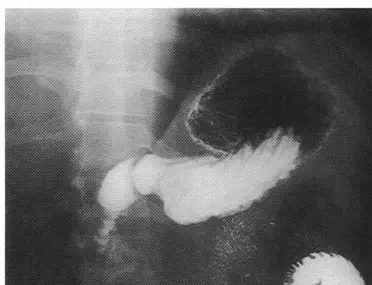

- 對比劑分布:影像中可見胃底(Fundus)呈現黑色透亮區,代表充滿空氣;而胃體(Body)、幽門部(Pylorus)及十二指腸球部(Duodenal bulb)則呈現白色高密度區,代表充滿了鋇劑。

- 解剖構造呈現:十二指腸球部與十二指腸C型環(C-loop)在影像中被完全展開(in profile),輪廓清晰,且沒有與胃體或脊椎產生嚴重的影像重疊。

- 體位推論:由於人體胃底的解剖位置較偏後側(Posterior),而胃體與幽門較偏前側(Anterior)。當病患處於「俯臥(Prone)」或「半俯臥」姿勢時,較重的鋇劑會受重力影響流向前側的胃體與幽門,而較輕的空氣則會往上浮至後側的胃底。反之,若病患為「仰臥(Supine)」,鋇劑則會聚積在胃底。因此,由影像中「胃底積氣、胃體/幽門積鋇」的特徵,可明確判定病患處於俯臥或半俯臥的姿勢。